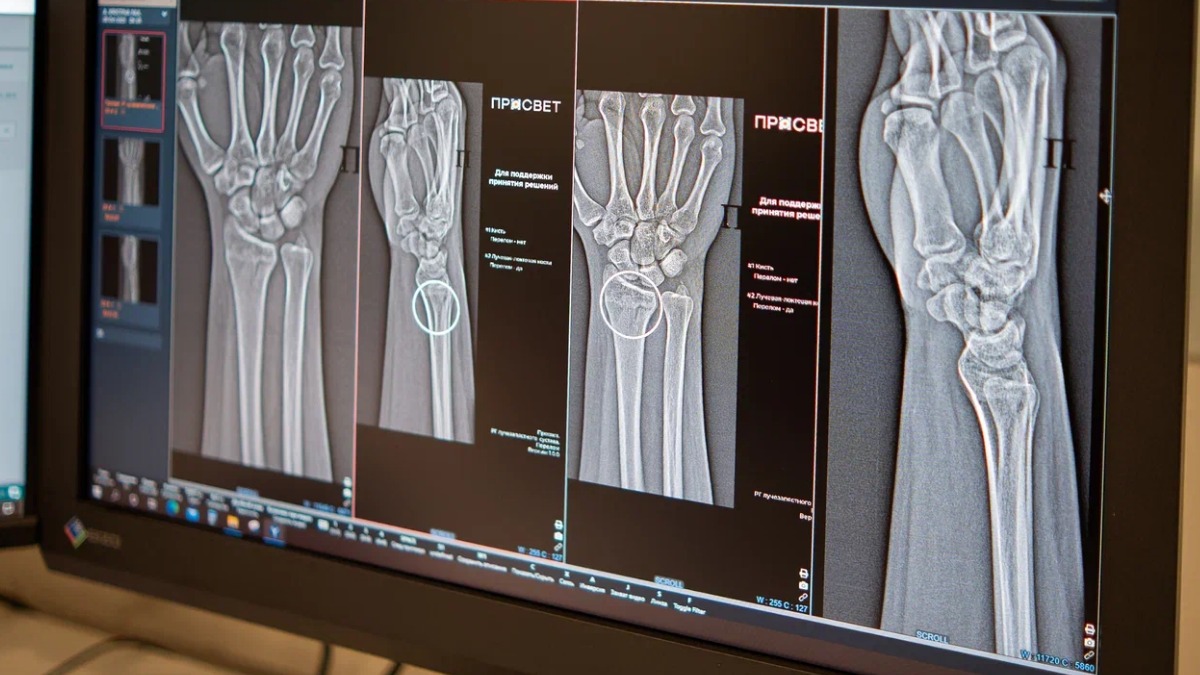

В Москве запустили два новых ИИ-сервиса для высокоточной диагностики множественных переломов голеностопного и лучезапястного суставов. Общее число разных по функционалу ИИ-сервисов для рентгенологов достигло 60. Об этом сообщила заместитель мэра Москвы по вопросам социального развития Анастасия Ракова.

— Цифровые решения уже более пяти лет помогают столичным рентгенологам — прежде всего в анализе медицинских снимков. Недавно мы запустили два новых ИИ-сервиса, которые помогают обнаруживать на рентгеновских изображениях травмы костей голеностопного и лучезапястного суставов — одних из самых функциональных и при этом уязвимых. Алгоритмы автоматически отметят поврежденные участки и выполнят необходимые измерения, даже если на снимке присутствуют признаки сразу нескольких переломов, — рассказала Анастасия Ракова.

ИИ-технологии в лучевой диагностике анализируют снимки по множеству параметров, помогают выполнять необходимые расчеты и ускоряют описание изображений. Они способны выявлять даже самые мелкие трещины и указывать врачу на наличие нескольких переломов в одной области. Корректная диагностика напрямую влияет на выбор тактики успешного лечения.